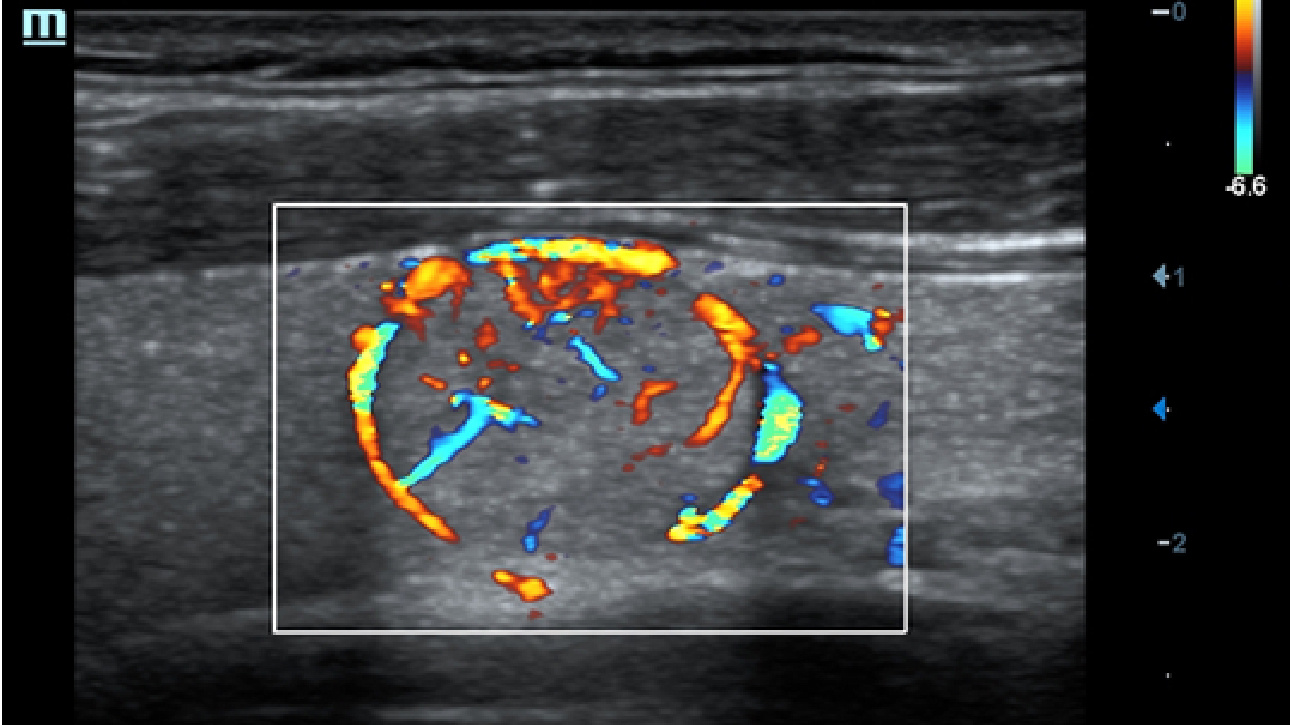

X-Insight es la soluci├│n intuitiva para una mejor visualizaci├│n.

La nueva soluci├│n de Mindray es una excelente transformaci├│n desde la continua comprensi├│n de las necesidades cl├Łnicas del usuario, combinada con la evoluci├│n de la tecnolog├Ła de los ultrasonidos m├Īs puntera. Repleto de vitalidad, con el ├║nico objetivo de visualizar el futuro y evitar los l├Łmites, el ec├│grafo DC-60Exp con X-Insight est├Ī constantemente mejorando con una escalabilidad aumentada. Como un socio personal, el equipo de ultrasonidos DC-60 Exp con X-Insight se centra en lo que verdaderamente importa, ayudando al usuario a administrar su pr├Īctica cl├Łnica con facilidad y seguridad.

Bas├Īndose en una profunda comprensi├│n de las necesidades del usuario, el sistema de ultrasonidos DC-60 Exp con X-Insight est├Ī dise?ado para ofrecer una alta eficiencia con im├Īgenes de precisi├│n, la cual se ve potenciada por una claridad inmediata, una inteligencia excepcional y benefici├Īndose de una c├│moda experiencia.